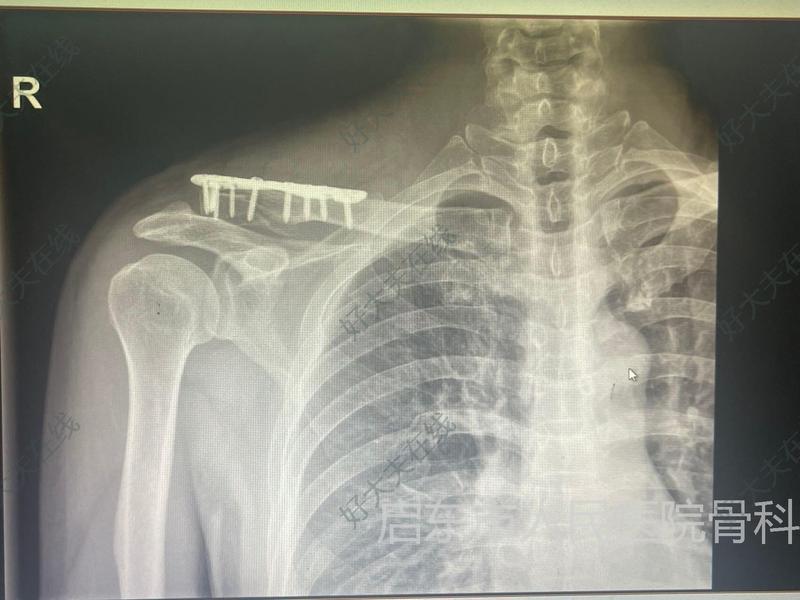

一位54岁男性车祸外伤患者,右锁骨远端骨折、左肩胛骨骨折、双侧多发肋骨骨折。经过手术治疗,使用锁骨远端钢板固定,患者右肩疼痛明显缓解,已经开始积极功能锻炼。

术中发现骨折远端粉碎性骨折,使用克氏针临时固定加肌腱线捆扎。采用锁骨远端钢板固定

患者右肩疼痛明显缓解,已经开始积极功能锻炼